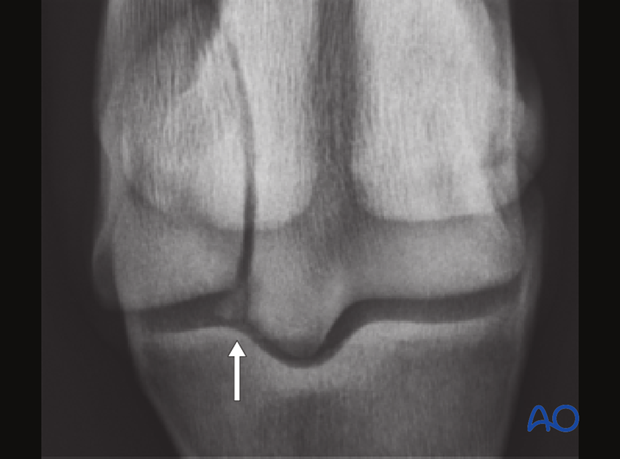

A full set of metacarpo/metatarsophalangeal joint radiographs should be taken as well as the tangential view silhouetting the distal palmar/plantar third metacarpal/metatarsal bone. The fracture is easily identified on the straight dorsopalmar/plantar projection, but the additional view is necessary to adequately evaluate the joint.

Recognition of comminution along the distal palmar/plantar margin of the bone is important in giving a preoperative prognosis.